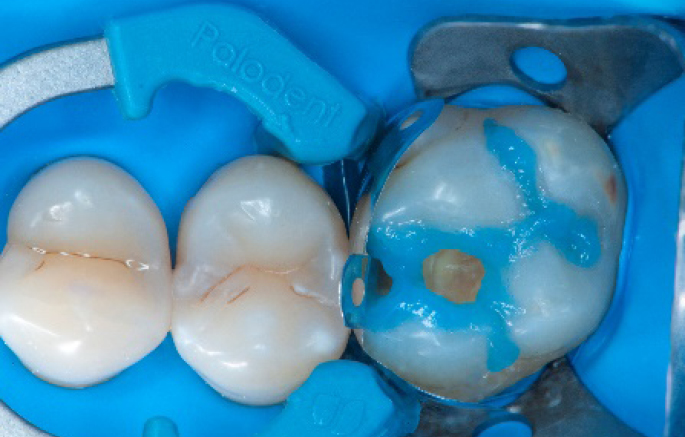

Step 6:

Selective enamel etching procedure with Conditioner2.

Step 7:

Adhesive application with a universal adhesive, Prime&Bond3.

Step 8:

Transformation of class II into class I, restoring the interproximal wall with Spectra ST4 composite in shade A2.